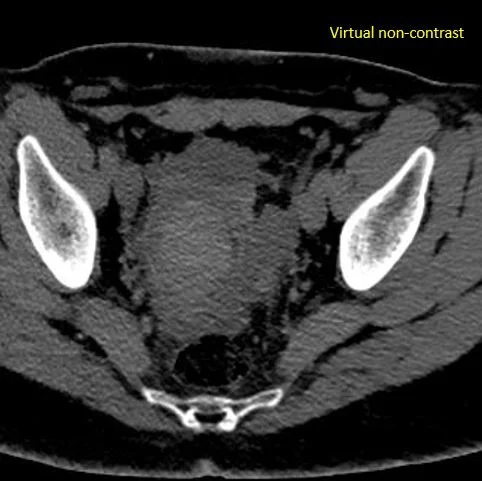

Virtual non-contrast: Dense clot in the mass.

CT scan obtained in the ED shows a complex right adnexal mass, about 60 HU. Turn on spectral CT, and you see it is made of non-enhancing clot, hyperdense on virtual non-contrast and without iodine uptake, inside the thin, enhancing lining of a cyst. The clot has a spectral curve that is flat, consistent with absent perfusion.